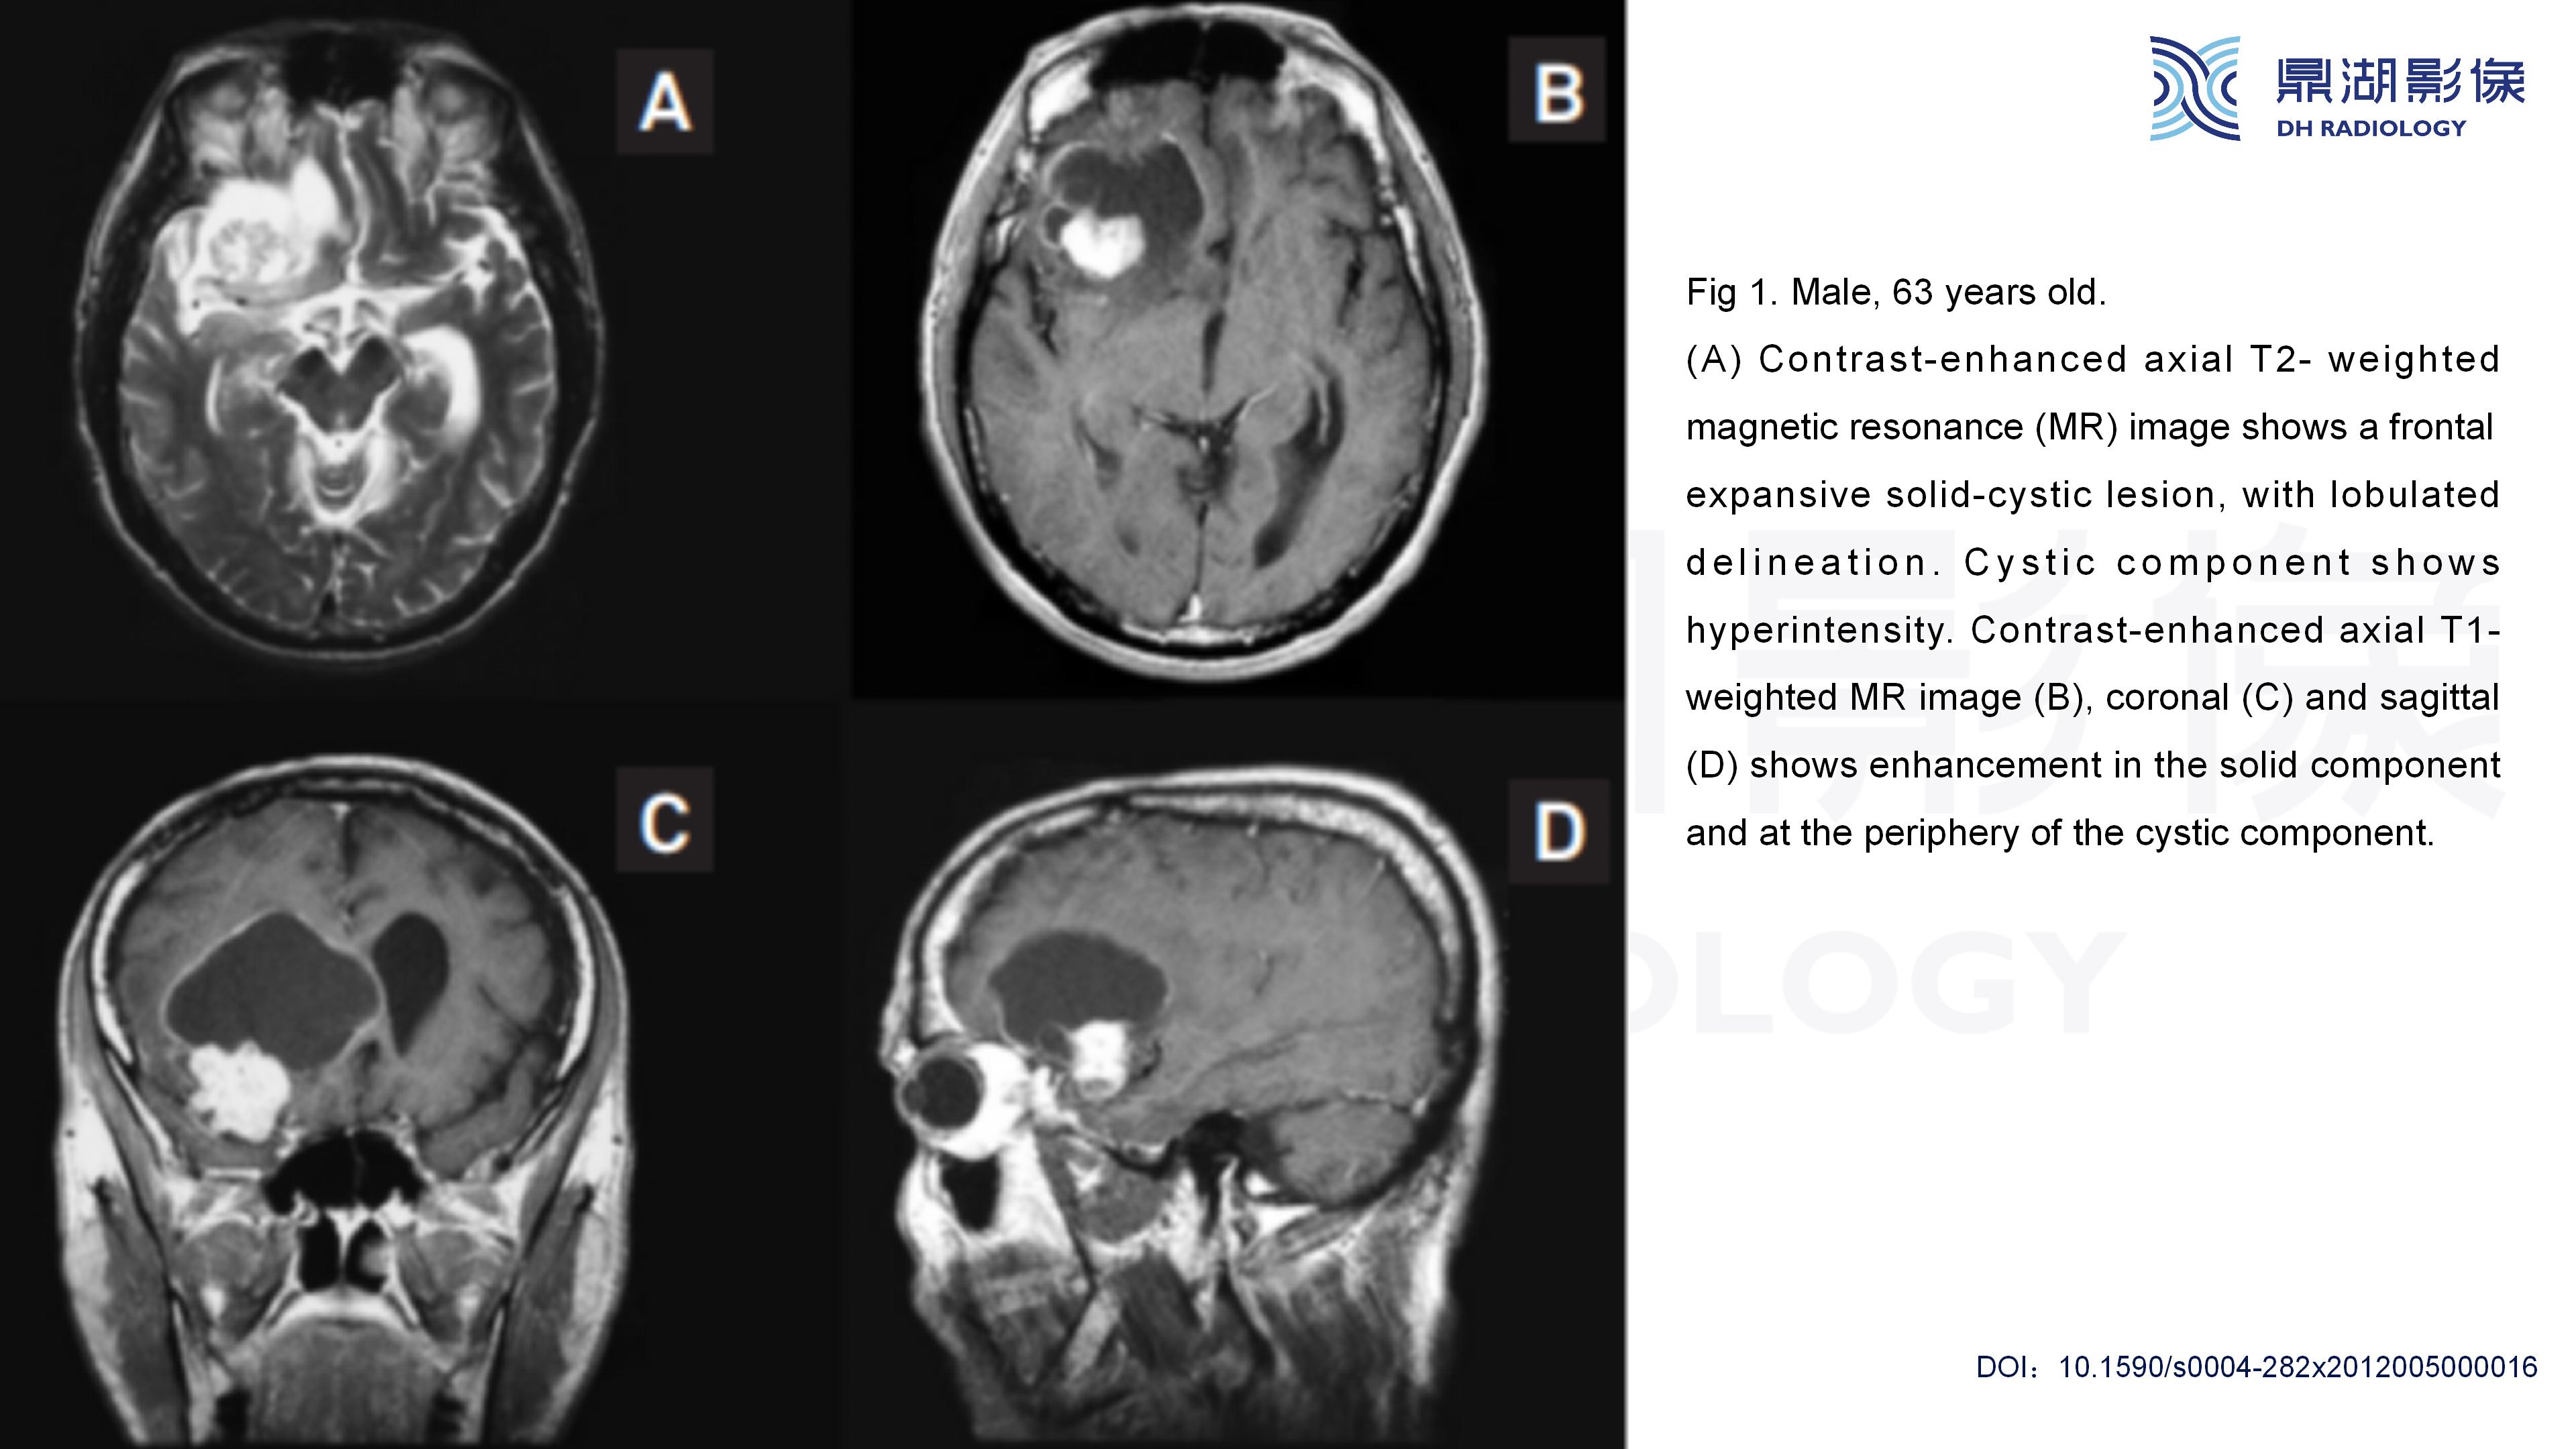

幕上毛细胞型星形细胞瘤(WHO Ⅰ级)